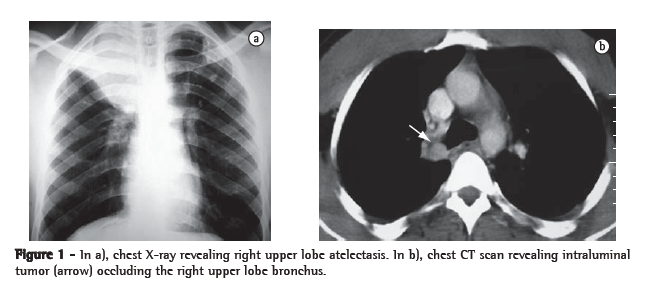

A 32-year-old male reported fever and dry cough 9 months prior to admission. On that occasion, he received treatment for pneumonia elsewhere, but the dry cough remained. The physical examination revealed right-sided wheezing, and a chest X-ray showed right upper lobe atelectasis (Figure 1a). A chest CT scan revealed an endobronchial lesion occluding the right upper lobe bronchus (Figure 1b), with no mediastinal lymph node enlargement. Fiberoptic bronchoscopy revealed an endobronchial tumor located in the right upper lobe bronchus. The tumor had a smooth, reddish surface and had obstructed the right upper lobe bronchus, without protruding into the right main bronchus. A biopsy provided inconclusive results. The patient underwent right thoracotomy with a presumed diagnosis of carcinoid tumor. Since the right upper lobe was atelectatic and fibrotic, we proceeded to a right upper lobectomy. The intraoperative histological examination demonstrated exiguous bronchial margins, and a wedge bronchoplasty was therefore performed. Radical mediastinal lymph node dissection was not performed. The patient had an uneventful recovery and was discharged on the fourth postoperative day.